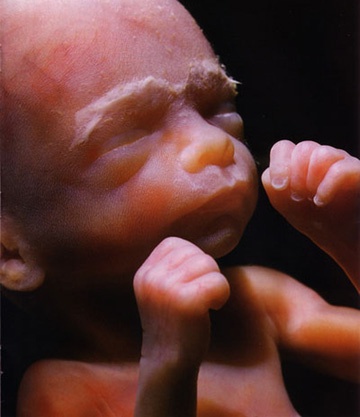

Как выглядит ребенок

Кожа малыша расправляется, становится менее морщинистой и светлеет. Подкожно-жировая клетчатка увеличивается. Лицо плода уже похоже на лицо новорожденного: выражен нос, сформированы веки, ресницы и брови, щечки округляются, ушные раковины занимают свое место и увеличиваются.

Большинство малышей уже лежат головкой вниз, но если он находится ягодичками вниз, время на переворот еще есть. Из-за уменьшения пространства движения становятся более ощутимыми.

Ваш малыш по размерам как помело, вес около 800 грамм, длина 320 мм (новорожденный имеет рост около 50 см), сердцебиение 120–160 уд./мин.